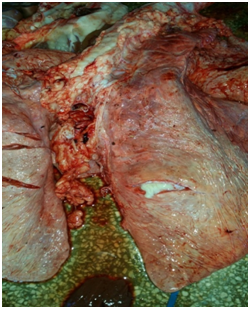

Lesions in cattle are most often found in organs rich in reticuloendothelial tissue, particularly the lungs and associated lymph nodes.25 Lesions are most commonly present in the lower respiratory tract, however the upper respiratory tract and its associated tissues also displays disease in many cases (Figure 1) (Figure 2).

Figure 1 Lung from a tuberculous cow showing calcified granulomas.

Figure 2 Lung lymph node from a tuberculous cow.

Bovine tuberculosis (BTB) is a disease characterized by formation of granulomatous nodules called tubercles whose locations depend largely on the route of infection. In calves, it is usually transmitted by ingestion and lesions involve the mesenteric lymph nodes Figure 3 with possible spread to other organs. In older cattle, infection is usually by the respiratory tract with lesions in the lung and dependent lymph nodes.26

Figure 3 Lung lymph node from a tuberculous cow.